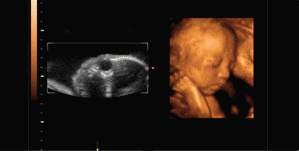

四、B超检查:可以尽早了解胎宝宝是否发育迟缓的情况。并且,此项检查还可以及时了解预产期。

四维彩超简称"4D",也就是四维成像技能,是先进的超声诊断技能,能直观、立体显示人体器官的三维结构及动态、实时地观察立体结构,广泛运用于对胎儿进行超声检查,立体观察宫内胎儿发育情况的同时,还能清晰显示胎儿在宫内的动态,让准爸爸准妈妈一起观看宝宝在妈妈肚子里的各种动作神态,另外还能制作成U盘,让宝宝拥有完整的0岁相册,留下有效的记忆。